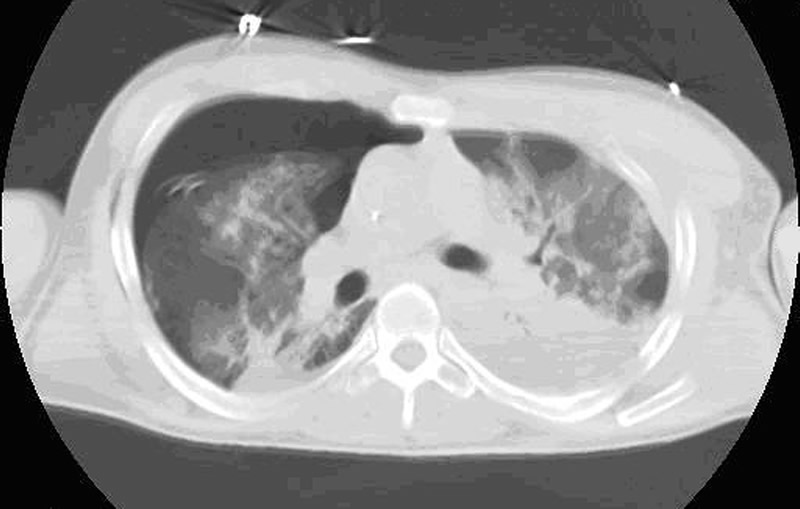

In patients with isolated blunt chest trauma who have severe flail chest without significant pulmonary contusion, prolonged internal pneumatic stabilization is not suitable because of the risk of ventilator-related infectious complications. Moreover, mechanical ventilation is not always successful in preventing chest wall deformities that may result in a subsequent respiratory restrictive dysfunction [10,11]. In patients with mild or no pulmonary contusions (Figure 2), early surgical stabilization (within few days of internal pneumatic stabilization) may result in shorter intensive care unit stay with lower morbidity and prevention of pulmonary restrictive complications resulting in working incapacity [9].